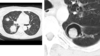

This CT scan was taken from a patient with longstanding neutropenia after their neutrophils bounced back. The patient presented with high fever and RUQ pain with nausea, vomiting and anorexia.

What is the name of this condition?

Hepatosplenic (chronic disseminated) candidiasis